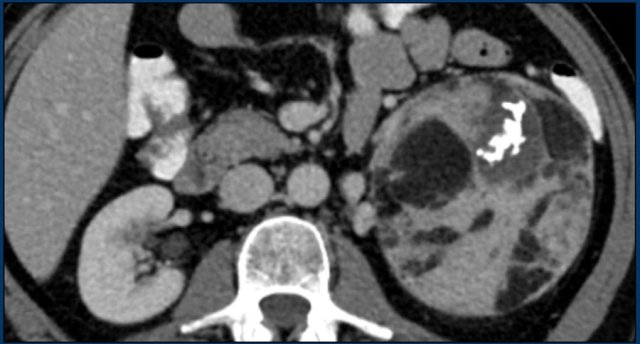

Pheochromocytoma Pheochromocytoma

This is a heterogeneously enhancing, relatively well-defined indeterminate lesion.

It proved to be a pheochromocytoma.